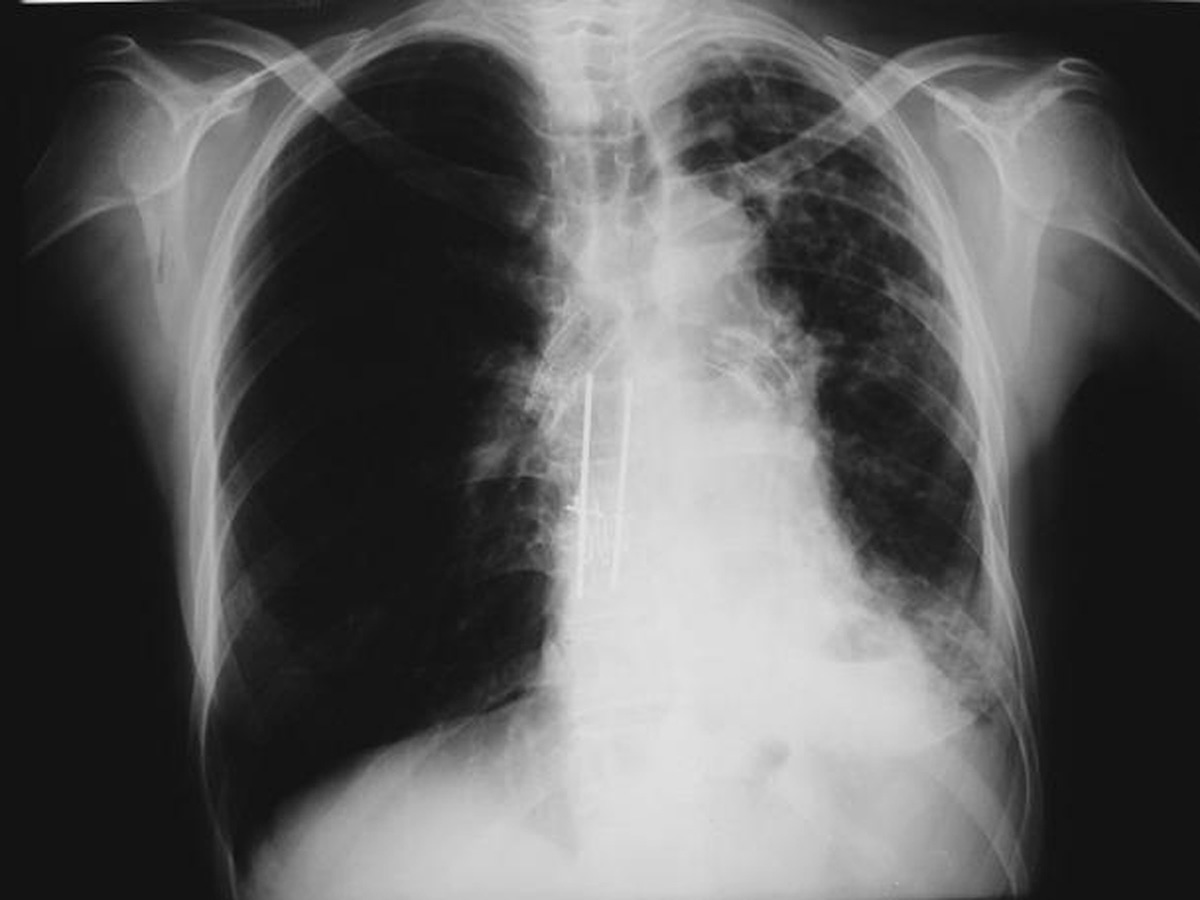

A number of indications for endoscopic treatment have been reported (Table 1) but the most frequent is lung cancer involving the airway proximal to the lobar orifices. In most patients with unresectable tumors only palliation is required [2,3] and sometimes urgent stenting during chemo-radiotherapy may be demanded; however, in selected patients a viable airway may be important as a bridge to surgery [4,5]. Patients with primary airway tumors (Figure 1) may receive benefit from endoluminal stenting if surgery is not indicated. Other tumors that occur adjacent to the airway may produce obstruction by direct invasion or extrinsic compression, including esophageal cancer possibly accompanied by tracheo-esophageal fistula (Figure 2), thyroid cancer, and other head and neck tumors, and may be successfully palliated with endoluminal treatments combined with stent placement [6].